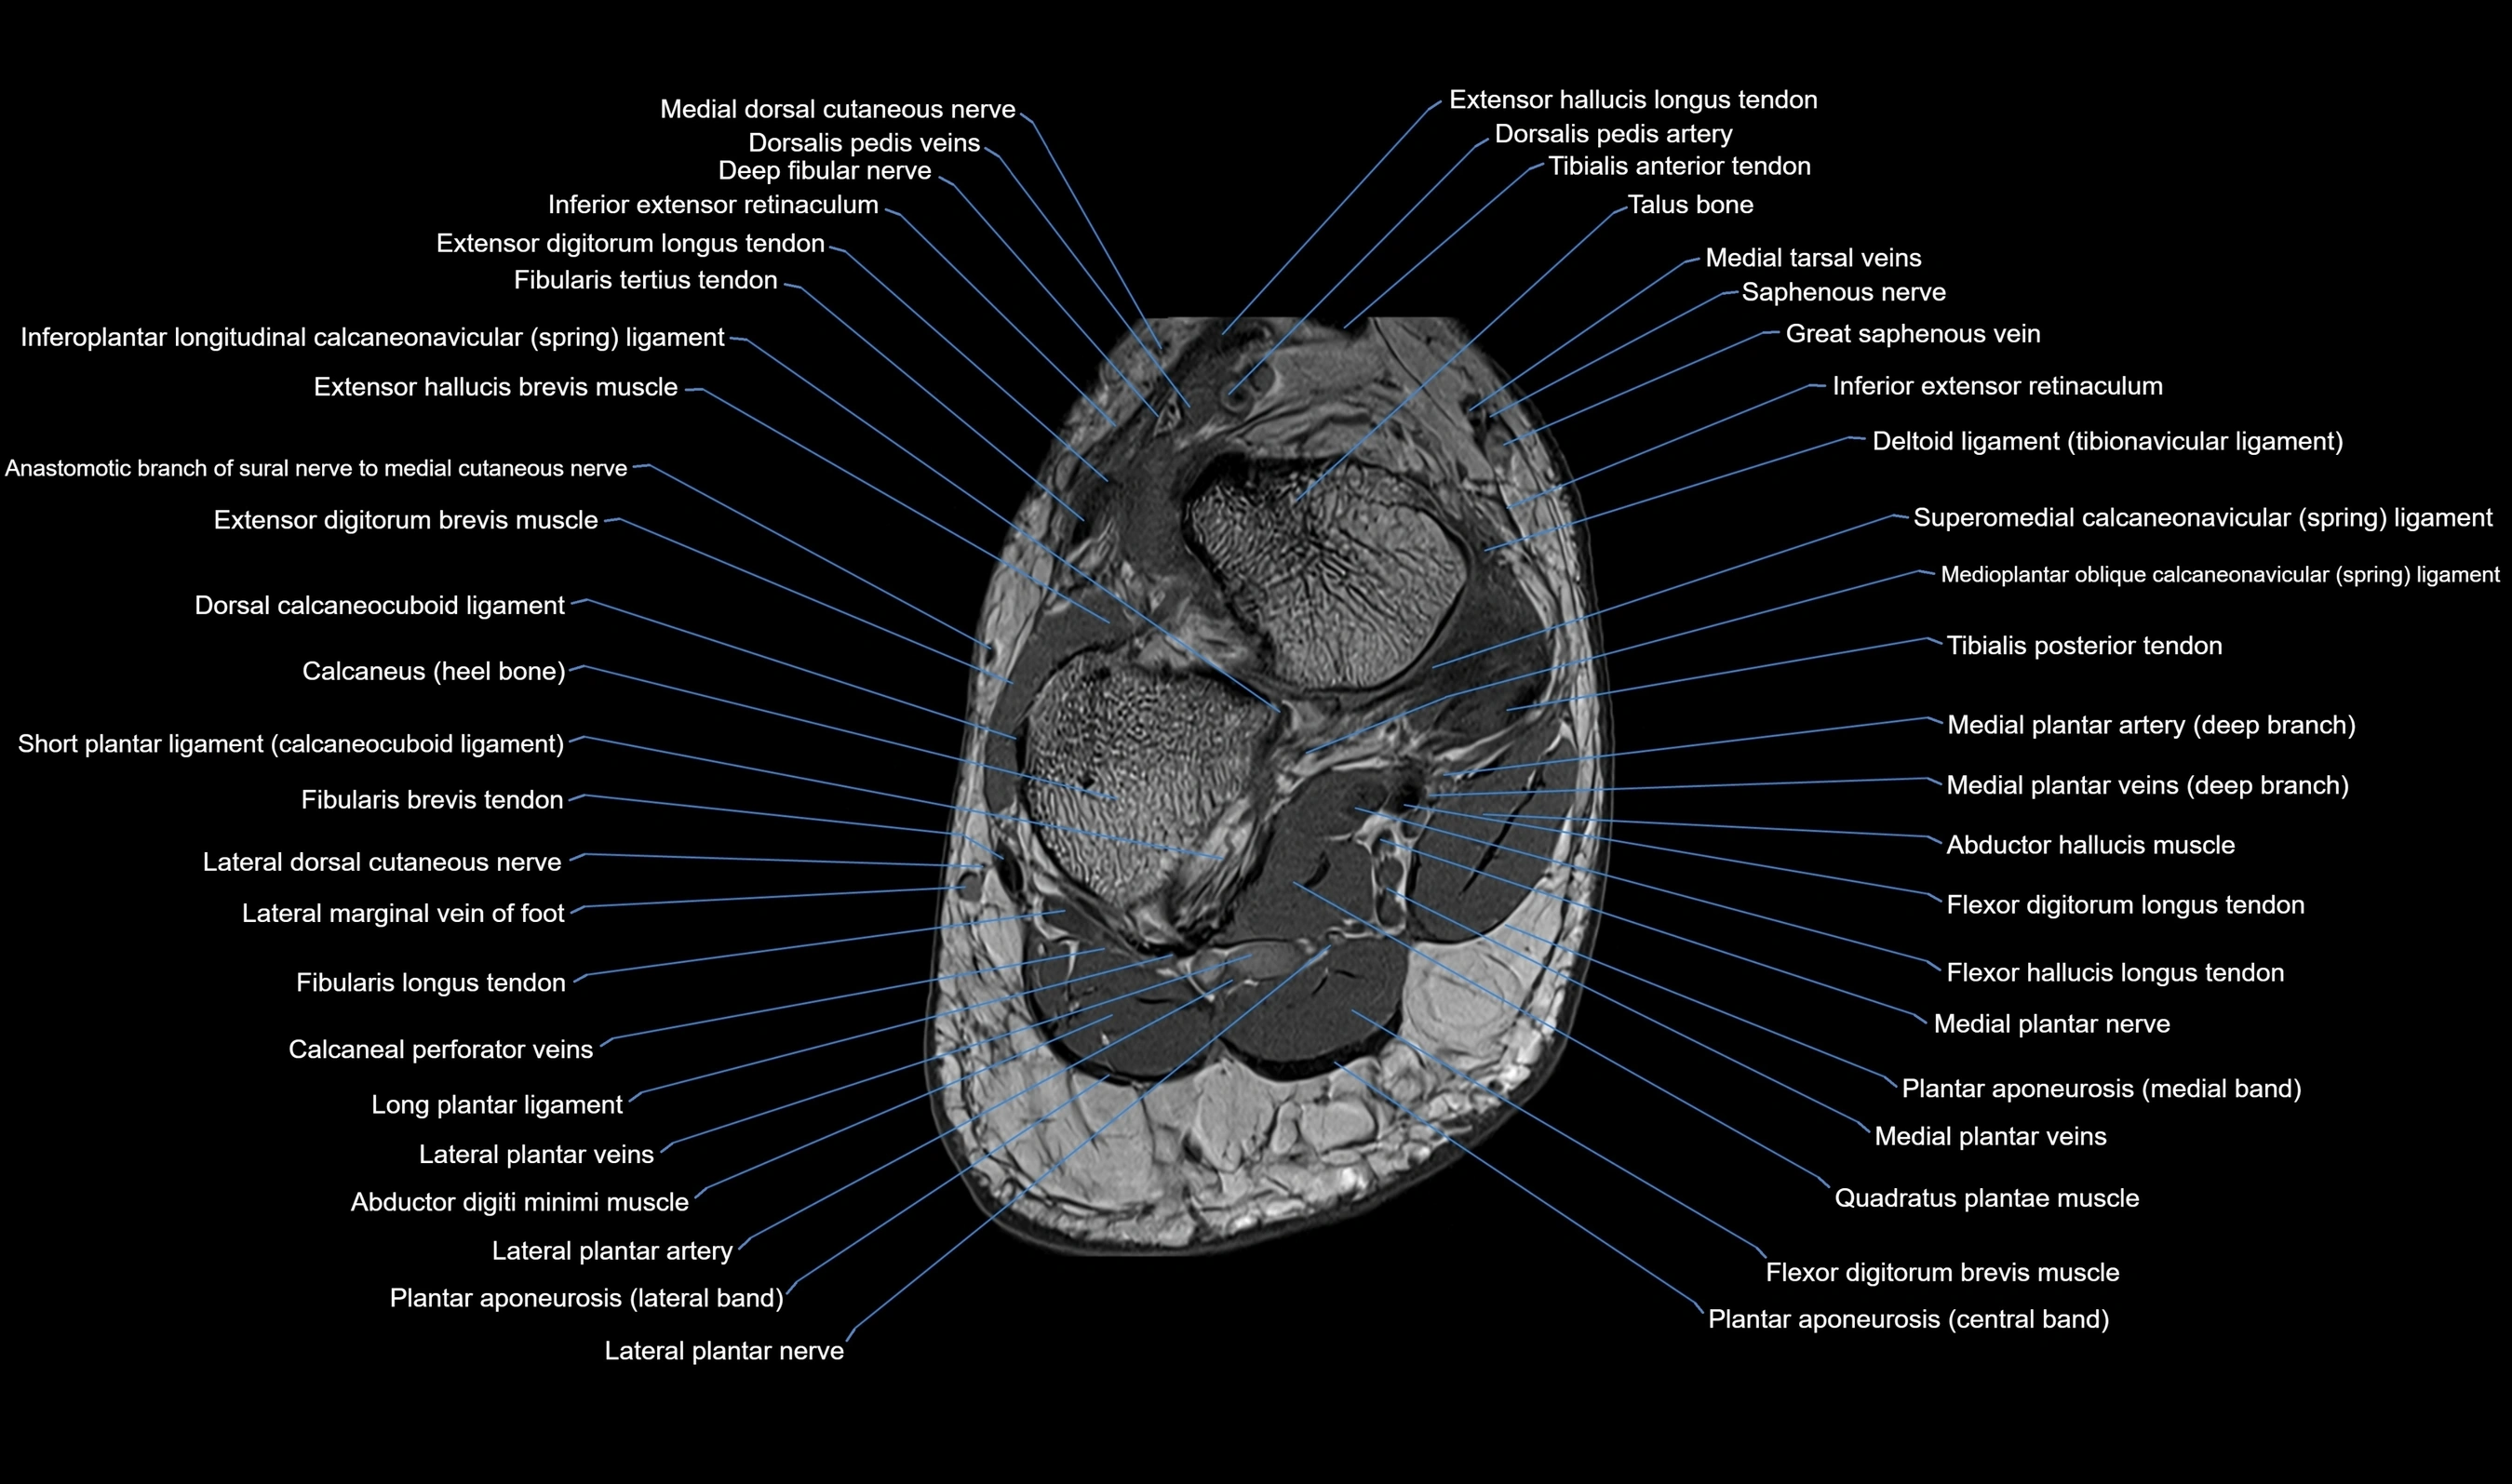

MRI image